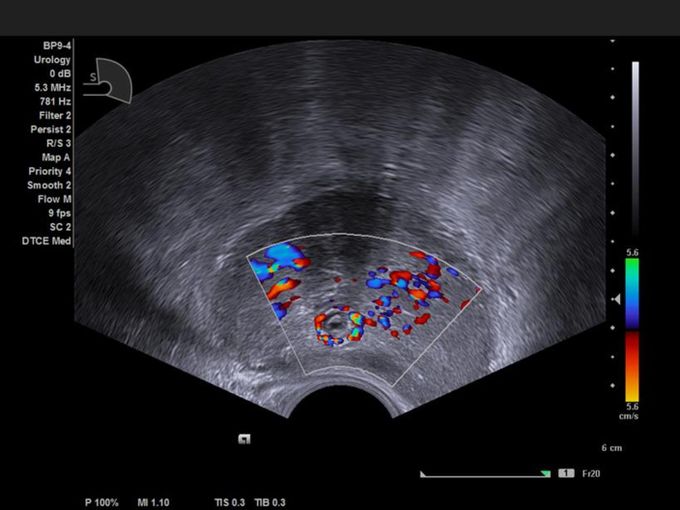

Кроме новой техники, можно заказать восстановленные медицинские системы: ультразвуковые сканеры, томографы, флюороскопы, ангиографы и хирургические установки С-дуга.